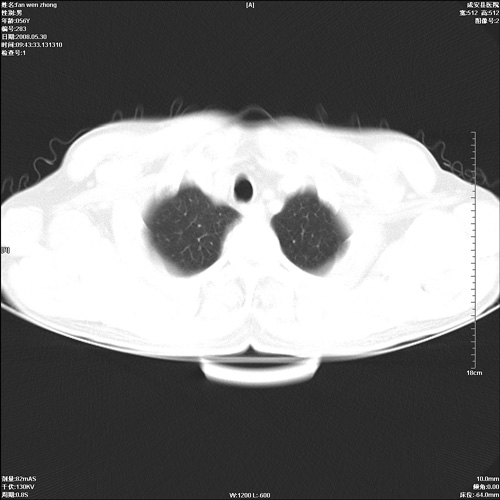

病人 男 56岁 一周前高热,体温达39-40度,经抗炎治疗后,体温渐降,达37,5-38度,轻微咳嗽,胸部不适 查白细胞为1.3万 行ct检查,请分析。

双肺内可见多发结节状病灶,并见小空洞,病人高热,白血球增高,应该是典型的迁徙性肺脓肿(多为金黄色葡萄球菌感染)。查一下口腔等其它部位有无感染灶。

双肺内可见多发结节状病灶,并见小空洞,病人高热,白血球增高,应该是典型的迁徙性肺脓肿(多为金黄色葡萄球菌感染)。建议治疗后复查.